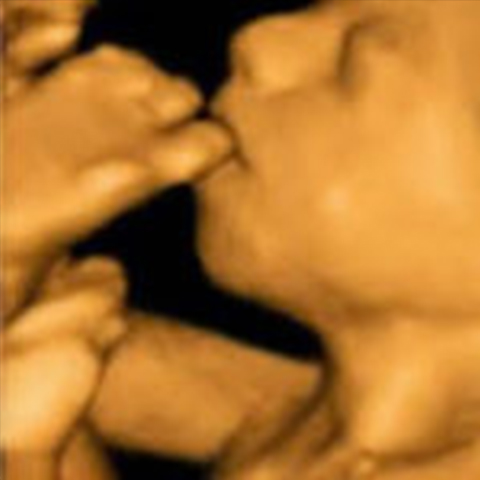

גלריה